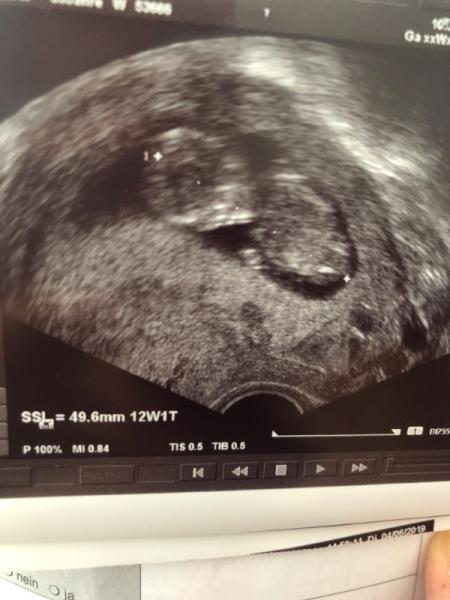

Hallo liebe mamis, Momentan befinde ich mich in der 12.ssw. Heute waren wir beim Frauenarzt zum Termin und es wurde natürlich geschalt. Es verläuft alles bestens, so wie es sein muss Sie sagte das die ersten 3 monate auch geschafft sind und das fehlgeburtsrisiko deutlich gesunken ist. Man soll ja dann die zeit lieber genießen Die maus hat sich nach dem wecken vom fa ordentlich bewegt, herzchen hat geschlagen. Und man hat gar nichts auffälliges entdeckt. Am liebsten würden wir mit meinem Partner das baby stundenlang im ultraschal beobachten. Es ist ein wunderschönes gefühl und sehr emotional. Wünsche allen eine weiterhin problemlose, gesunde kugelzeit